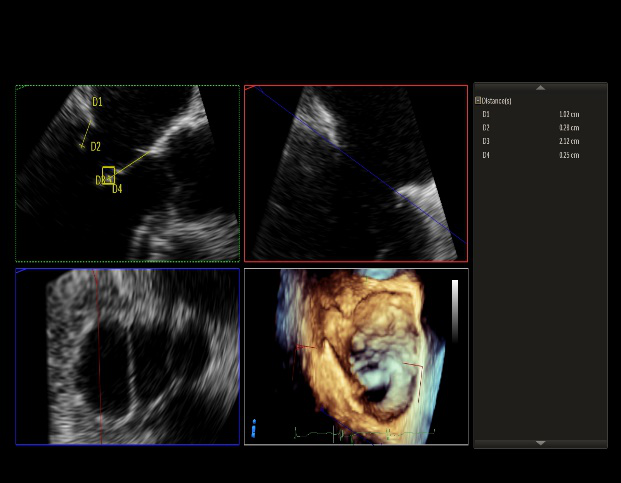

术前超声诊断:

长轴:左室下后壁节异,LAV:101ml,LVEDV:239ml

Bicom:MR(重度),返流束宽15.8mm,返流面积10.6cm²

PISA法定量EROA:0.69cm²,Rvol:168ml,RF:55%

肺静脉血流频谱呈收缩期反向

3D MV View

3D-color MV view:血流主要来源于2区近3区

Qlab软件勾画估测瓣口面积约:6.16cm²

二尖瓣口平均跨瓣压差:1mmHg

TEE Bicom返流量评估

TEE 4-Ch view返流量评估